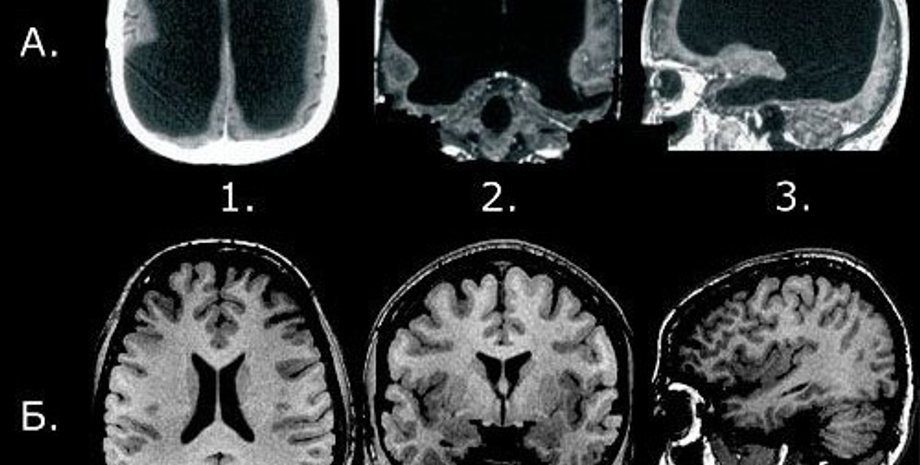

Медики из университета Эдинбурга (Великобритания) рассмотрели почти 20 тысяч случаев сканирования мозга, проведенных по различным причинам. Среди людей, которым делали мозговую томографию, никто не имел никаких симптомов основных заболеваний мозга.

Неврологи зафиксировали, что даже при обнаружении случайных аномалий работы мозга в 3% случаев (таких как ослабленные кровеносные сосуды или доброкачественная опухоль) не существовало четких медицинских доказательств проведения лечения для таких пациентов.